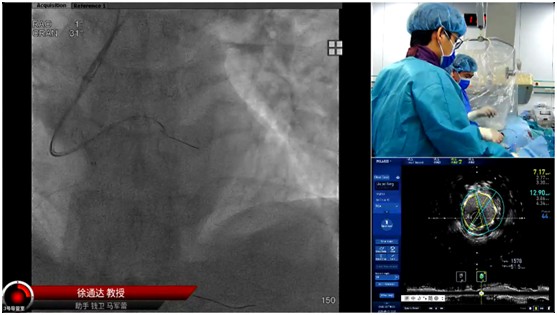

本屆大會的一大亮點當(dāng)數(shù)CTO手術(shù)演示環(huán)節(jié),CTO病變被視為冠心病介入治療領(lǐng)域的 "最后堡壘"。大會特邀多位國內(nèi)CTO介入領(lǐng)域頂尖專家同臺競技,進行了16臺高難度手術(shù)的實時直播演示,受到業(yè)內(nèi)普遍關(guān)注及高度評價。本次手術(shù)演示不僅展示了徐醫(yī)附院心內(nèi)科在區(qū)域內(nèi)雄厚的技術(shù)實力,更通過病例討論、技術(shù)培訓(xùn)等環(huán)節(jié),推動先進經(jīng)驗向基層輻射。參會的基層醫(yī)師普遍表示,專家們對復(fù)雜病例的處理策略和創(chuàng)新技術(shù)的應(yīng)用示范,為臨床實踐提供了寶貴參考。

閉幕式上,大會主席徐通達教授總結(jié)指出,本屆交流會通過思想碰撞與技術(shù)展示的深度融合,為心血管防治事業(yè)注入了新活力。徐州醫(yī)科大學(xué)附屬醫(yī)院心內(nèi)科將持續(xù)發(fā)揮區(qū)域醫(yī)療中心作用,推動學(xué)術(shù)成果轉(zhuǎn)化與人才培養(yǎng),為實現(xiàn) "健康中國 2030" 心血管健康目標貢獻力量。